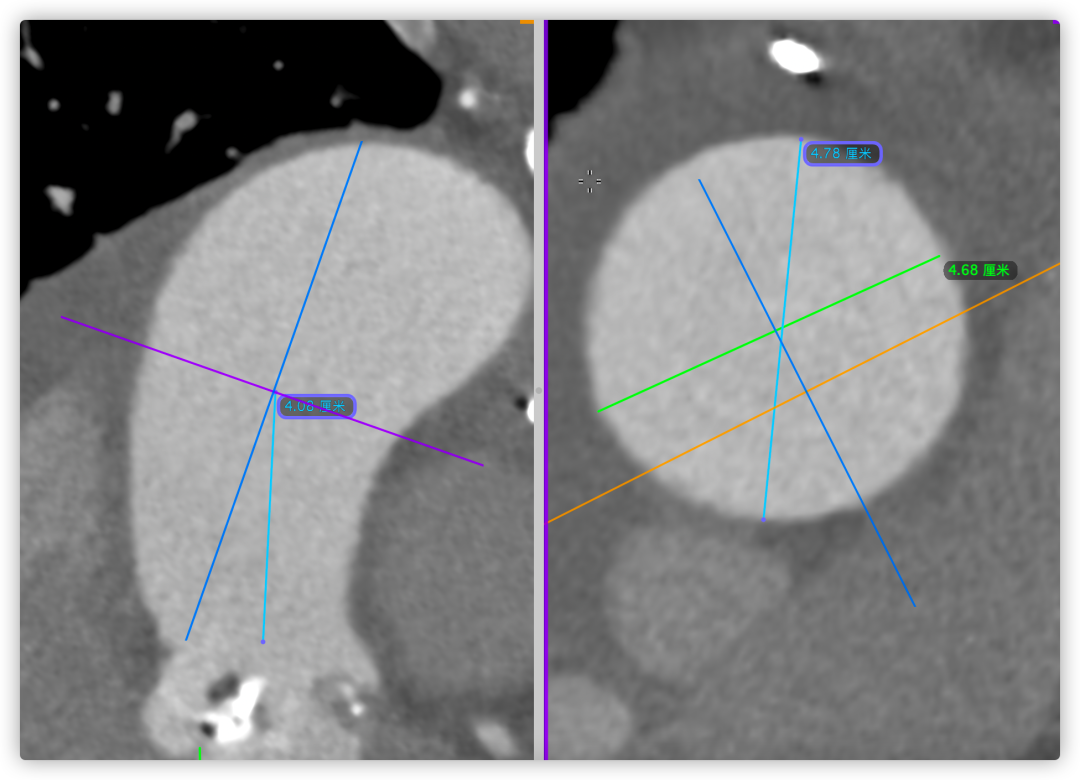

主动脉根部CT断层

根部角度/瓣环/左室流出道

左冠风险评估